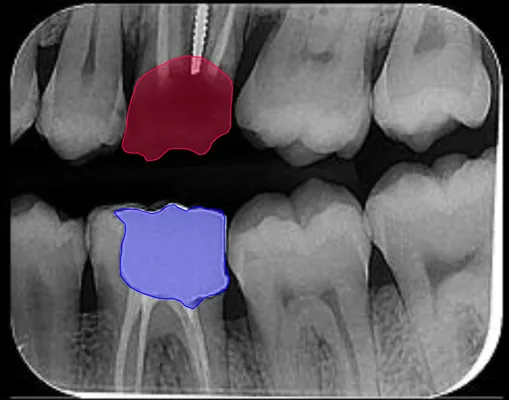

From leading R&D efforts at SmarTeeth and Smartory Startups to

working as a Computer Vision Engineer and Data Scientist at

APAC AI & Control, I've consistently developed software that

bridges cutting-edge tech with real-world needs, especially in

medical image analysis. I also spent time as a research